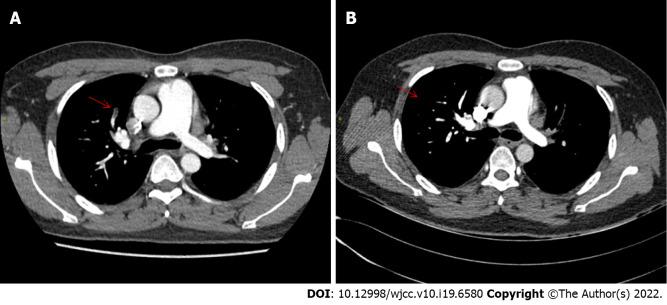

CASE SUMMARY

Here, we describe a 31-year-old male patient with chromosome 47, XXY type, who suffered deep vein thrombosis of the lower limbs accompanied by abnormal antiphospholipid antibody, lupus anticoagulant and factor VIII. After treatment with immunoadsorption therapy, glucocorticoids, cyclophosphamide, intravenous immunoglobulin and anticoagulant therapy, the patient showed dramatic symptomatic improvement. During the follow-up, the patient did not develop any new thrombotic events.